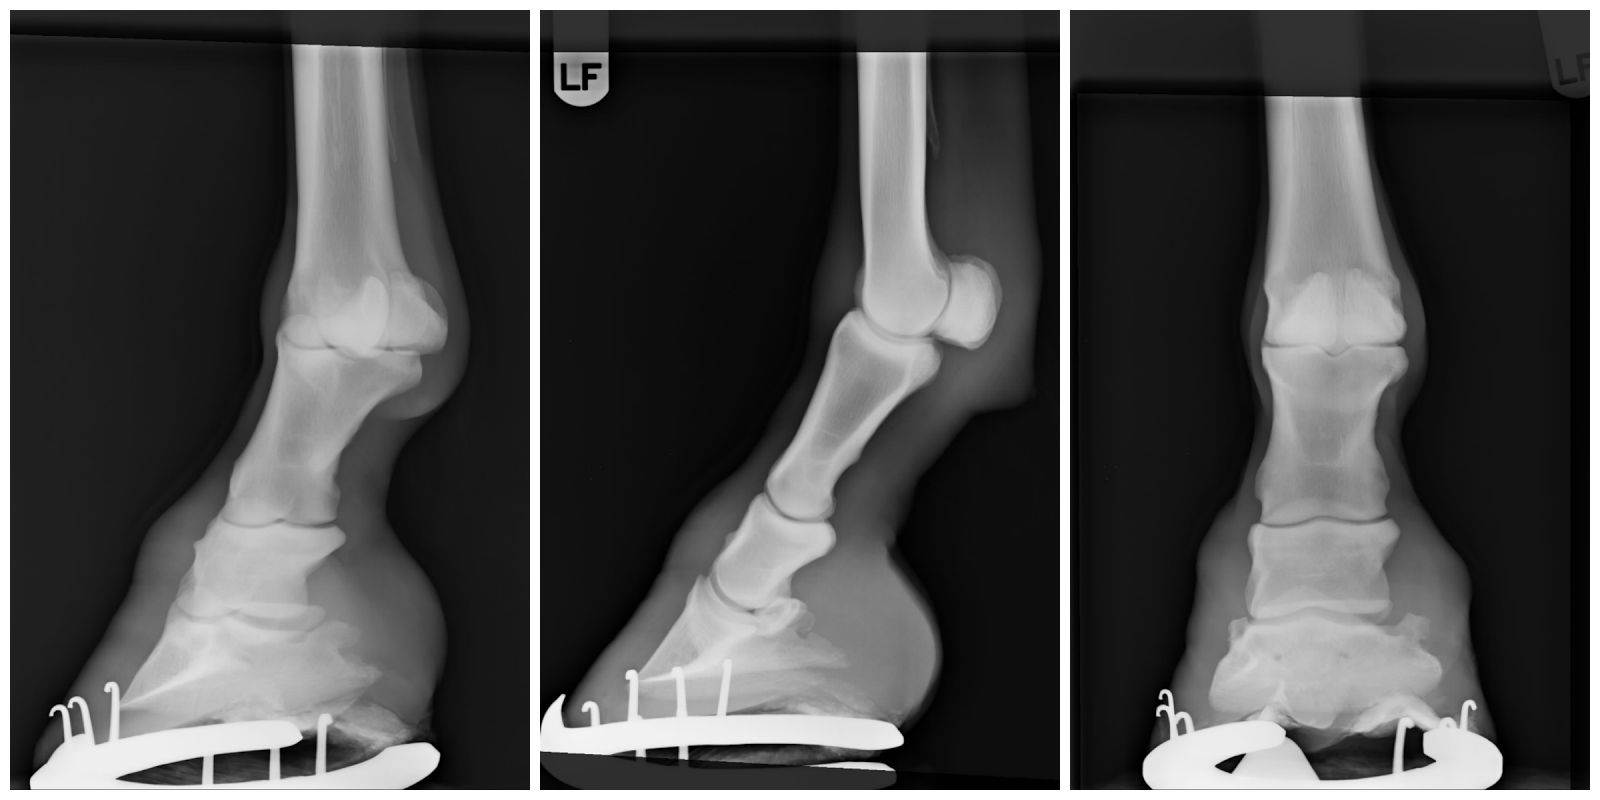

Vasen etujalka, tämä on piikitetty vuosi aikaisemminkin

Olimme klinikkareissulla 19.7, jonne lähdimme vasemman etujalan kuluman takia ikäänkuin vuosihuoltoon, ihan siinä mielessä että piikitetään vain vasen etukoipi. Reissu ei jäänytkään näin lyhyeksi ja simppeliksi, vaan päätimme ottaa kunnon ontumatutkimuksen ja röntgenkuvat kaikista jaloista.

Oikea etujalka, edes vähän paremman näköinen

Ratsastuskoulutaustaisen vanhan ponin jalat eivät olleet mitään kauneinta katsottavaa.

Sunnylta löytyi hieman lisääntyneen kuluman lisäksi takajaloista pahat kinnerpatit, oikeassa takajalassa ärhäkämpi kaveri ja sen lisäksi luupiikki.

Emme voi kuin yrittää hidastaa sen kasvua ja yrittää parhaamme mukaan lievittää ponin kipuja.

Oikea takajalka, selvästi pahempi kinnerpatti ja luupiikki.

Tämä jalka on aiheuttanut vasemman etujalan pahemman kuluman,

sillä oikea takajalka ja vasen etujalka ovat ristikkäiset parit ja näin ollen vaikuttavat toisiinsa.

Vasen takajalka